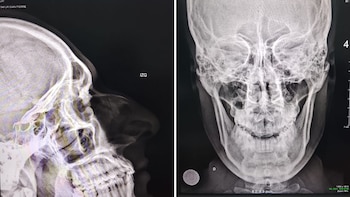

En medio de esa diligencia, el exfuncionario habría aprovechado un descuido para reaccionar de forma violenta. Las cámaras de seguridad captaron el instante en que toma de la cabeza al suboficial Reátegui Tafur y le propina tres rodillazos en el rostro, específicamente en la nariz. El ataque fue tan rápido como agresivo, y provocó que el efectivo cayera en una situación de evidente desventaja dentro de la sala, y terminó por fracturarle el tabique.

La gravedad de la lesión quedó confirmada luego de la evaluación médica. Según informó la familia del agente, el suboficial continúa con tratamiento a base de analgésicos, antibióticos y una próxima inmovilización con yeso, para corregir la fractura y evitar mayores complicaciones respiratorias. Incluso se indicó que, en una siguiente etapa, requerirá una operación para su recuperación total.